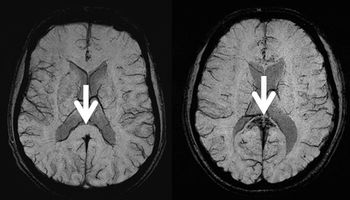

CHICAGO - High-altitude cerebral edema, the end stage of severe acute mountain sickness - once thought to be reversible - causes microbleeding on the brain.